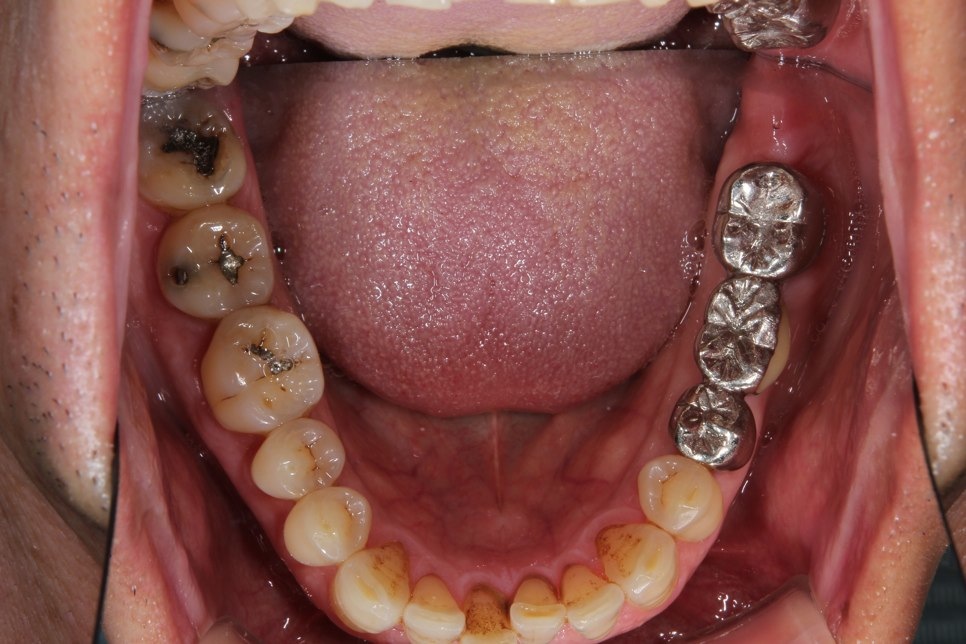

右下のダイレクトボンディング

費用5万円×2本

リスクとして欠ける可能性がある(修復可能)。